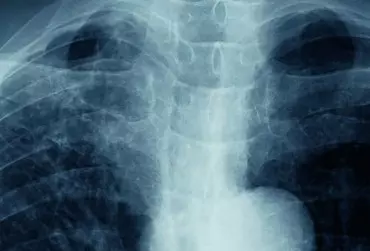

Rehabilitacja chorych z wysiękowym zapaleniem opłucnej

Wysiękowe zapalenie opłucnej może towarzyszyć wielu chorobom płuc. Powoduje u chorego duszności i ból w klatce piersiowej. Rehabilitację pacjenta należy rozpocząć zaraz po rozpoznaniu choroby, równocześnie z rozpoczęciem leczenia farmakologicznego. Ma ona na celu poprawę mechaniki oddechowej oraz powrót do możliwie jak największej sprawności sprzed choroby.